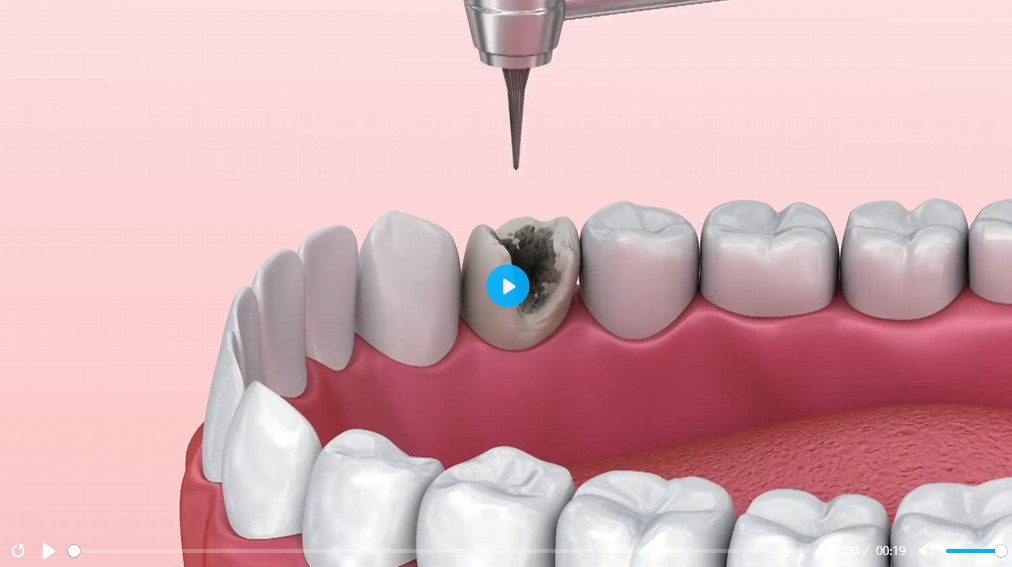

Let’s look at what receiving an inlay or onlay involves…

During the Procedure, Your Dentist Will…

Your dentist will simply remove any compromised tissue before placing the restoration.

Numb the Tooth

Administer a local anesthetic to numb the area for a more comfortable experience

Clear Out Decay

Remove compromised tissue to eliminate all damaged areas and bacteria

Clean the Area

Thoroughly clean and dry the tooth to ensure that no bacteria are trapped underneath the restoration

Take Impressions

Take impressions of the tooth, which will serve as the basis of the customized restoration

Revise Fit

Check the fit of the restoration to ensure your bite is balanced and comfortable

Attach Restoration

Bond the inlay or onlay to your tooth, restoring function and aesthetics